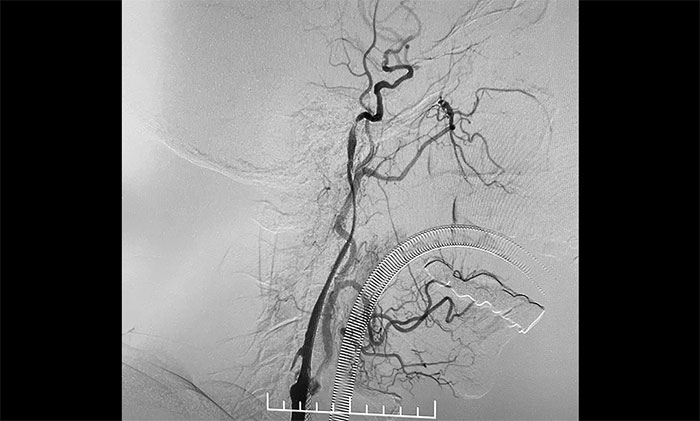

▲ 左侧颈内动脉闭塞顺利开通

术中,超滑导丝、多功能导管经过反复尝试顺利通过左颈内动脉起始段,到达左颈内动脉远端显影段,路图见远端血管通畅,左大脑中动脉显影;随后,微导丝经多功能导管置于左颈内动脉海绵窦段,经微导丝送入保护伞至左颈内动脉岩骨垂直段并释放,再沿保护伞微导丝送入4x30mm球囊于左颈内动脉起始段,给予球囊扩张,撤除球囊后造影见左颈内动脉起始段再通,左颈内动脉、左大脑中动脉显影;最后,送入9x50mm支架,释放于左颈内动脉颈段至左颈总动脉末段,造影见左颈内动脉起始段显影明显改善,左颈内动脉、左大脑中动脉、左大脑前动脉显影可,行3D造影见左颈内动脉颈段显影改善。行支架CT见支架成形可,行XperCT未见颅内出血。

手术圆满完成,席刚明教授团队、麻醉科团队及导管室团队通力合作,耐心、仔细地克服了手术的所有难点。左颈内动脉从“无”到“有”,正所谓“精诚所至,金石为开”,顺利为患者解除危机。

术后,王老先生无新发神经功能缺损。头晕、行走不稳、颈部僵硬感消失,肢体活动自如,说话流利,对答如流。目前,正在进一步康复中。